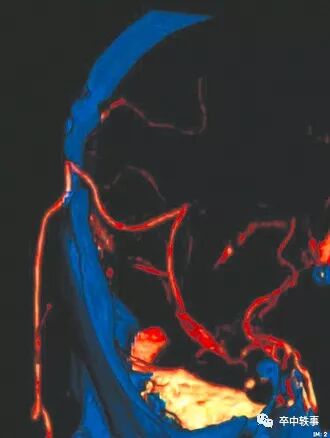

在医学院上解剖课时,我们知道有四条入颅血管,双侧的颈内动脉和左右的椎动脉 (上图)。